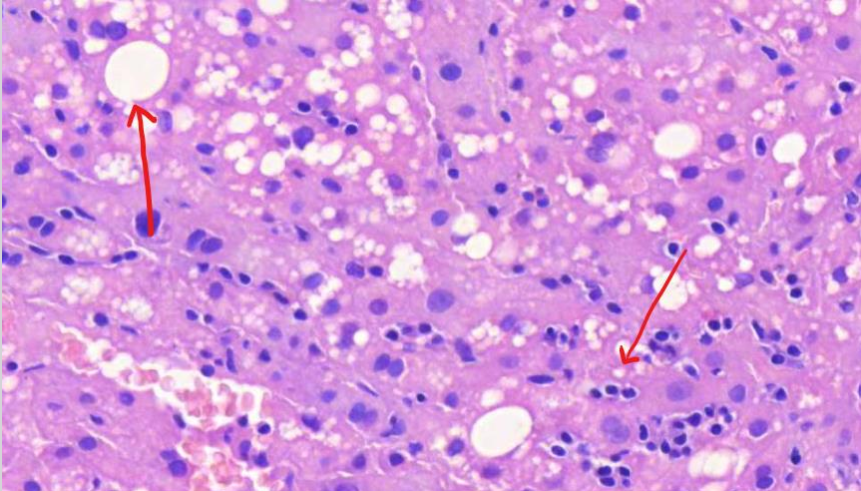

mitä kuvassa näkyy? (vinkki: onkosytooma)

onkosytooma

MIKÄ TAUTI? Kasvainsolujen tumat ovat pyöreitä. Sytoplasmaa on runsaasti, ja se on osin rakeista ja granulaarista.